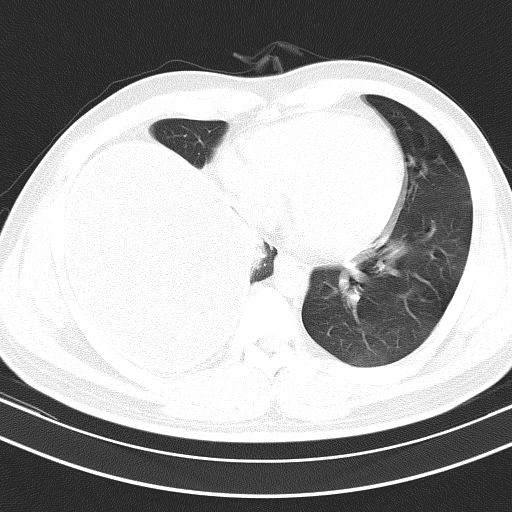

胸水ct图片

腹腔积液.左侧后胸壁可见弧形水样低低密度影,边缘清 - 抖音

这种大量胸水,千万别做胸腔穿刺

术前胸部ct示胸腔积液

胸部ct(2011年12月19日引流900ml胸腔积液后):左侧胸腔积液伴左肺下叶

【影像读片】胸腔积液 | ct报告书写 | 基础知识分享